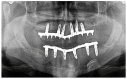

Optimal functional outcomes in oncologic patients with squamous cell carcinoma (SCCA) of the tongue and floor of the mouth require good lingual mobility, adequate facial competence, the cheek suction effect and dental rehabilitation with osseointegrated implants. In this study, twenty-two oncologic patients who had been diagnosed with intraoral SCCA affecting the tongue and the floor of the mouth and who had undergone wide resection of the tumor and immediate reconstruction with an inferiorly pedicled FAMM flap and immediate osseointegrated implants were assessed. Lingual mobility, speech articulation, deglutition, implant success rate, mouth opening, and aesthetic results were evaluated. All patients were staged as T2 and the defect size ranged from 3.7 × 2.1 cm to 6.3 × 4.2 cm. A selective neck dissection was performed in all patients as part of their oncologic treatment, either electively or for node positive disease. Thirteen patients (59%) were diagnosed with node positive disease and underwent adjuvant radiotherapy. A total of 101 osseointegrated implants were placed for prosthetic rehabilitation and 8 implants were lost (7.9%), of which 7 received radiotherapy (87.5%). The implant success rate was 92.1%. Mouth opening was reported as normal in 19 patients (86.3%). Tongue tip elevation was reported as excellent in 19 patients (86.3%) and good in 3 patients (13.6%). Lingual protrusion was referred to as excellent in 15 patients (68.2%) and good in 6 patients (27.2%). Lateral excursion was reported as excellent in 14 patients (63.6%) and good in 7 patients (31.8%). In terms of speech articulation, 20 patients reported normal speech (90.9%). Regarding deglutition, 19 patients (86.3%) reported a regular diet while a soft diet was reported by 3 patients (13.7%). Aesthetic results were referred to as excellent in 17 patients (77.3%). FAMM flaps, immediate implants and fixed prostheses enable the functional rehabilitation of oncologic patients, optimizing aesthetics and functional outcomes even in patients undergoing irradiation, thus returning oncologic patients to an excellent quality of life.